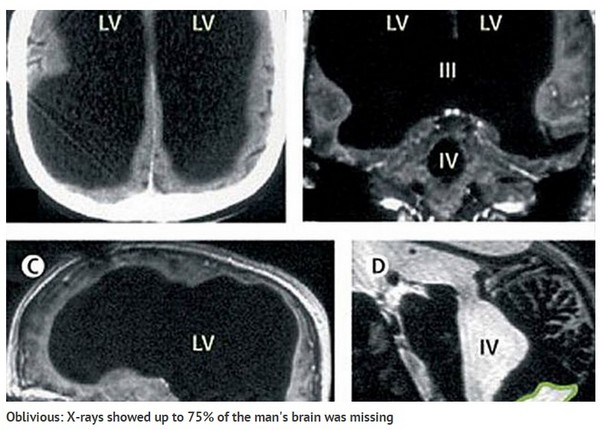

法男大脑缩小了约50~75%的面积。

针对这起特殊事件进一步追踪发现,原来男子六个月大时罹患脑积水,医生当时曾以流管方式排水,直到14岁时才移走,没想到其实没有根治,男子之后30年脑部仍持续积水,渐渐造成他的脑物质被分解,最后丧失了50%到75%的面积。

案例研究员弗耶(Lionel Feuillet)指出,男子的左右脑均有缩小,该区域是负责控制动作、情感、认知、语言等功能,理应严重影响生活,但男子却能照常过日子,推测脑部能随着时间自行重组修复,由大脑尚未毁损的地方负责其它部分工作。